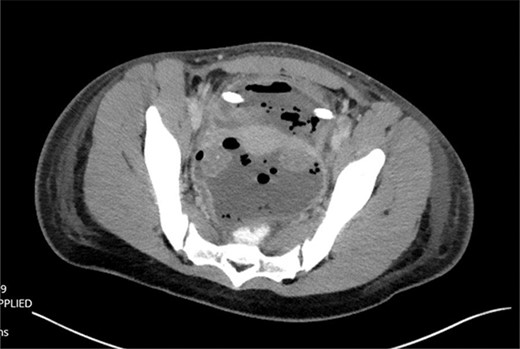

Patient is a 21-year-old female who presented with severe, sudden onset abdominal pain with associated poor oral intake, nausea and vomiting. Patient’s only past medical history was remarkable for normocytic anemia found on lab work. Patient did not report any significant family history. As a part of the patient’s initial work-up a computed tomography (CT) of the abdomen and pelvis with IV contrast was obtained with evidence of intussusception of a long segment of small bowel in the lower midline abdomen extending into the pelvis, measuring ~15 cm in length (Fig. 1); the patient’s CT was not remarkable for pneumatosis or obstruction.